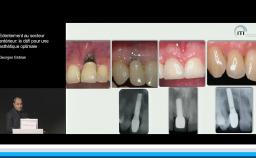

Après avoir fait une revue exhaustive de la littérature sur les principes biologiques conduisant à la résorption des tables osseuses alvéolaires après une extraction, Mark Bischof aborde l’historique des techniques qui ont été proposées depuis 20 ans pour préserver l’intégrité et l’apparence des tissus osseux et muqueux dans le cadre de réhabilitations prothétiques implant-portées. Reposant sur la littérature, il nous propose une lecture critique et argumentée des différentes options qui seront illustrées de cas cliniques démonstratifs.